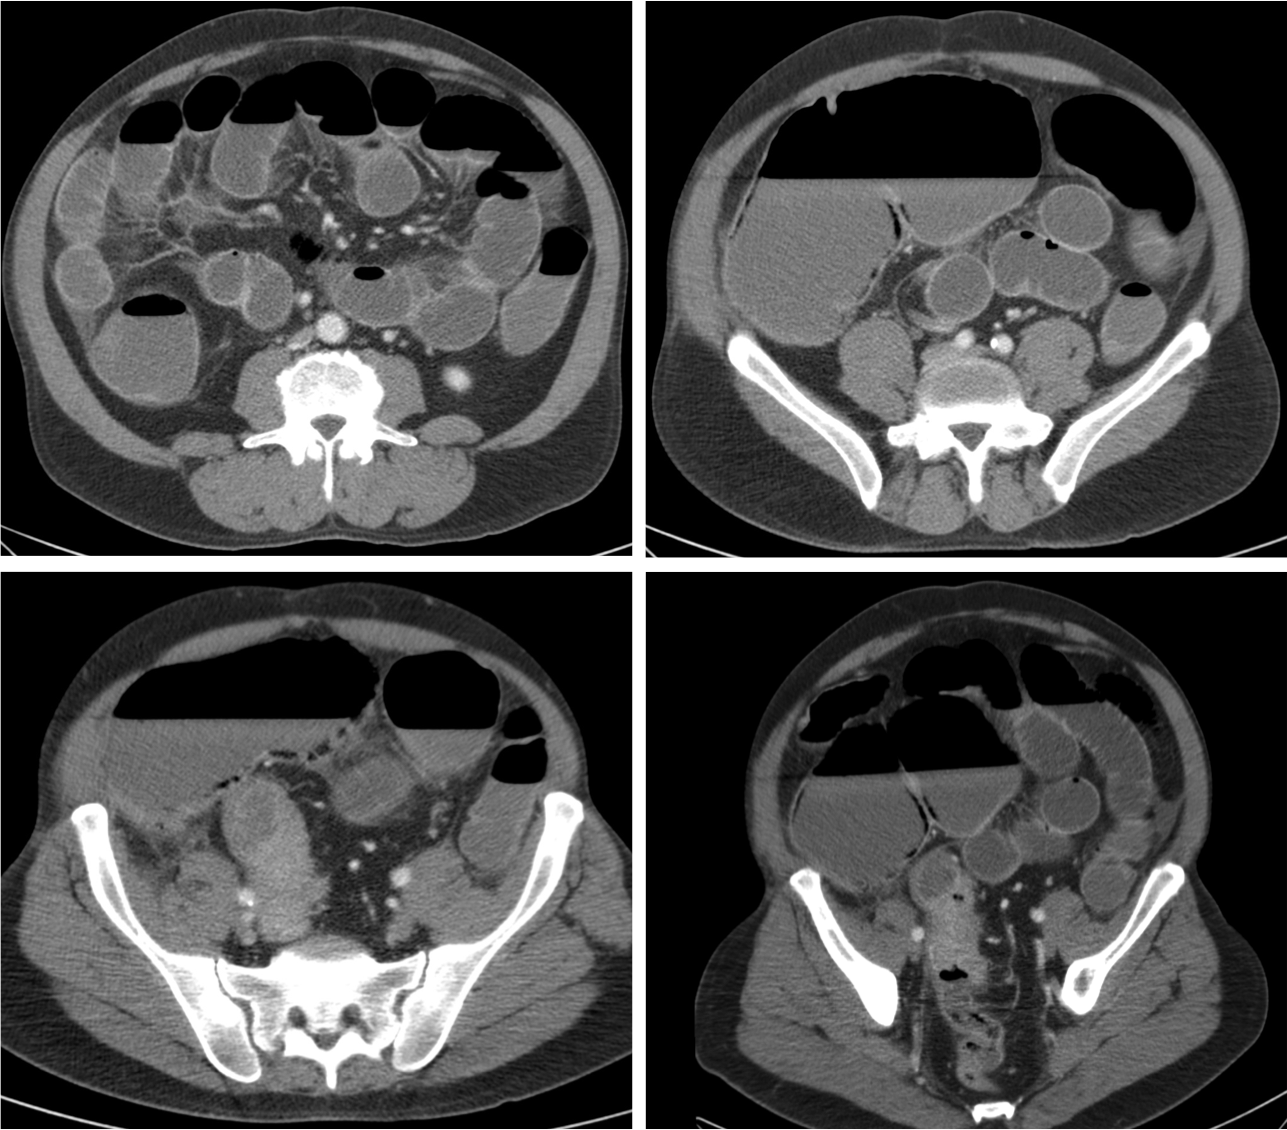

El diagnóstico actual de la se realiza mediante TC abdominal:

- El hallazgo patognomónico es el signo de la escarapela o diana identificable en la TC o ecografía.

- Podemos ver la imagen de “Intestino dentro de intestino” gracias a las reconstrucciones multiplanares.

Invaginación de Intestino Delgado

- Son más frecuentes que las de colon

- Es más frecuente la invaginación esporádica. Si hay lesión subyacente, suele ser benigna.

- Las causas malignas son menos frecuentes (15-30%), en general metástasis, sobre todo de melanoma.

- El linfoma constituye el 20-40% de todos los tumores malignos de ID.

Invaginación de Intestino Grueso

- Suele deberse a una lesión subyacente, sobre todo procesos malignos primarios.

- Resto son causas benignas (lipomas, polipos adenomatosos) o idiopáticas.

- Díficil determinar la causa subyacente, excepto en el lipoma (atenuación grasa) o si existe enfermedad metastásica abdominal conocida.

- El lipoma constituye la causa benigna más frecuente de invaginación colo-cólica y el adenocarcinoma de colon la causa maligna más frecuente.